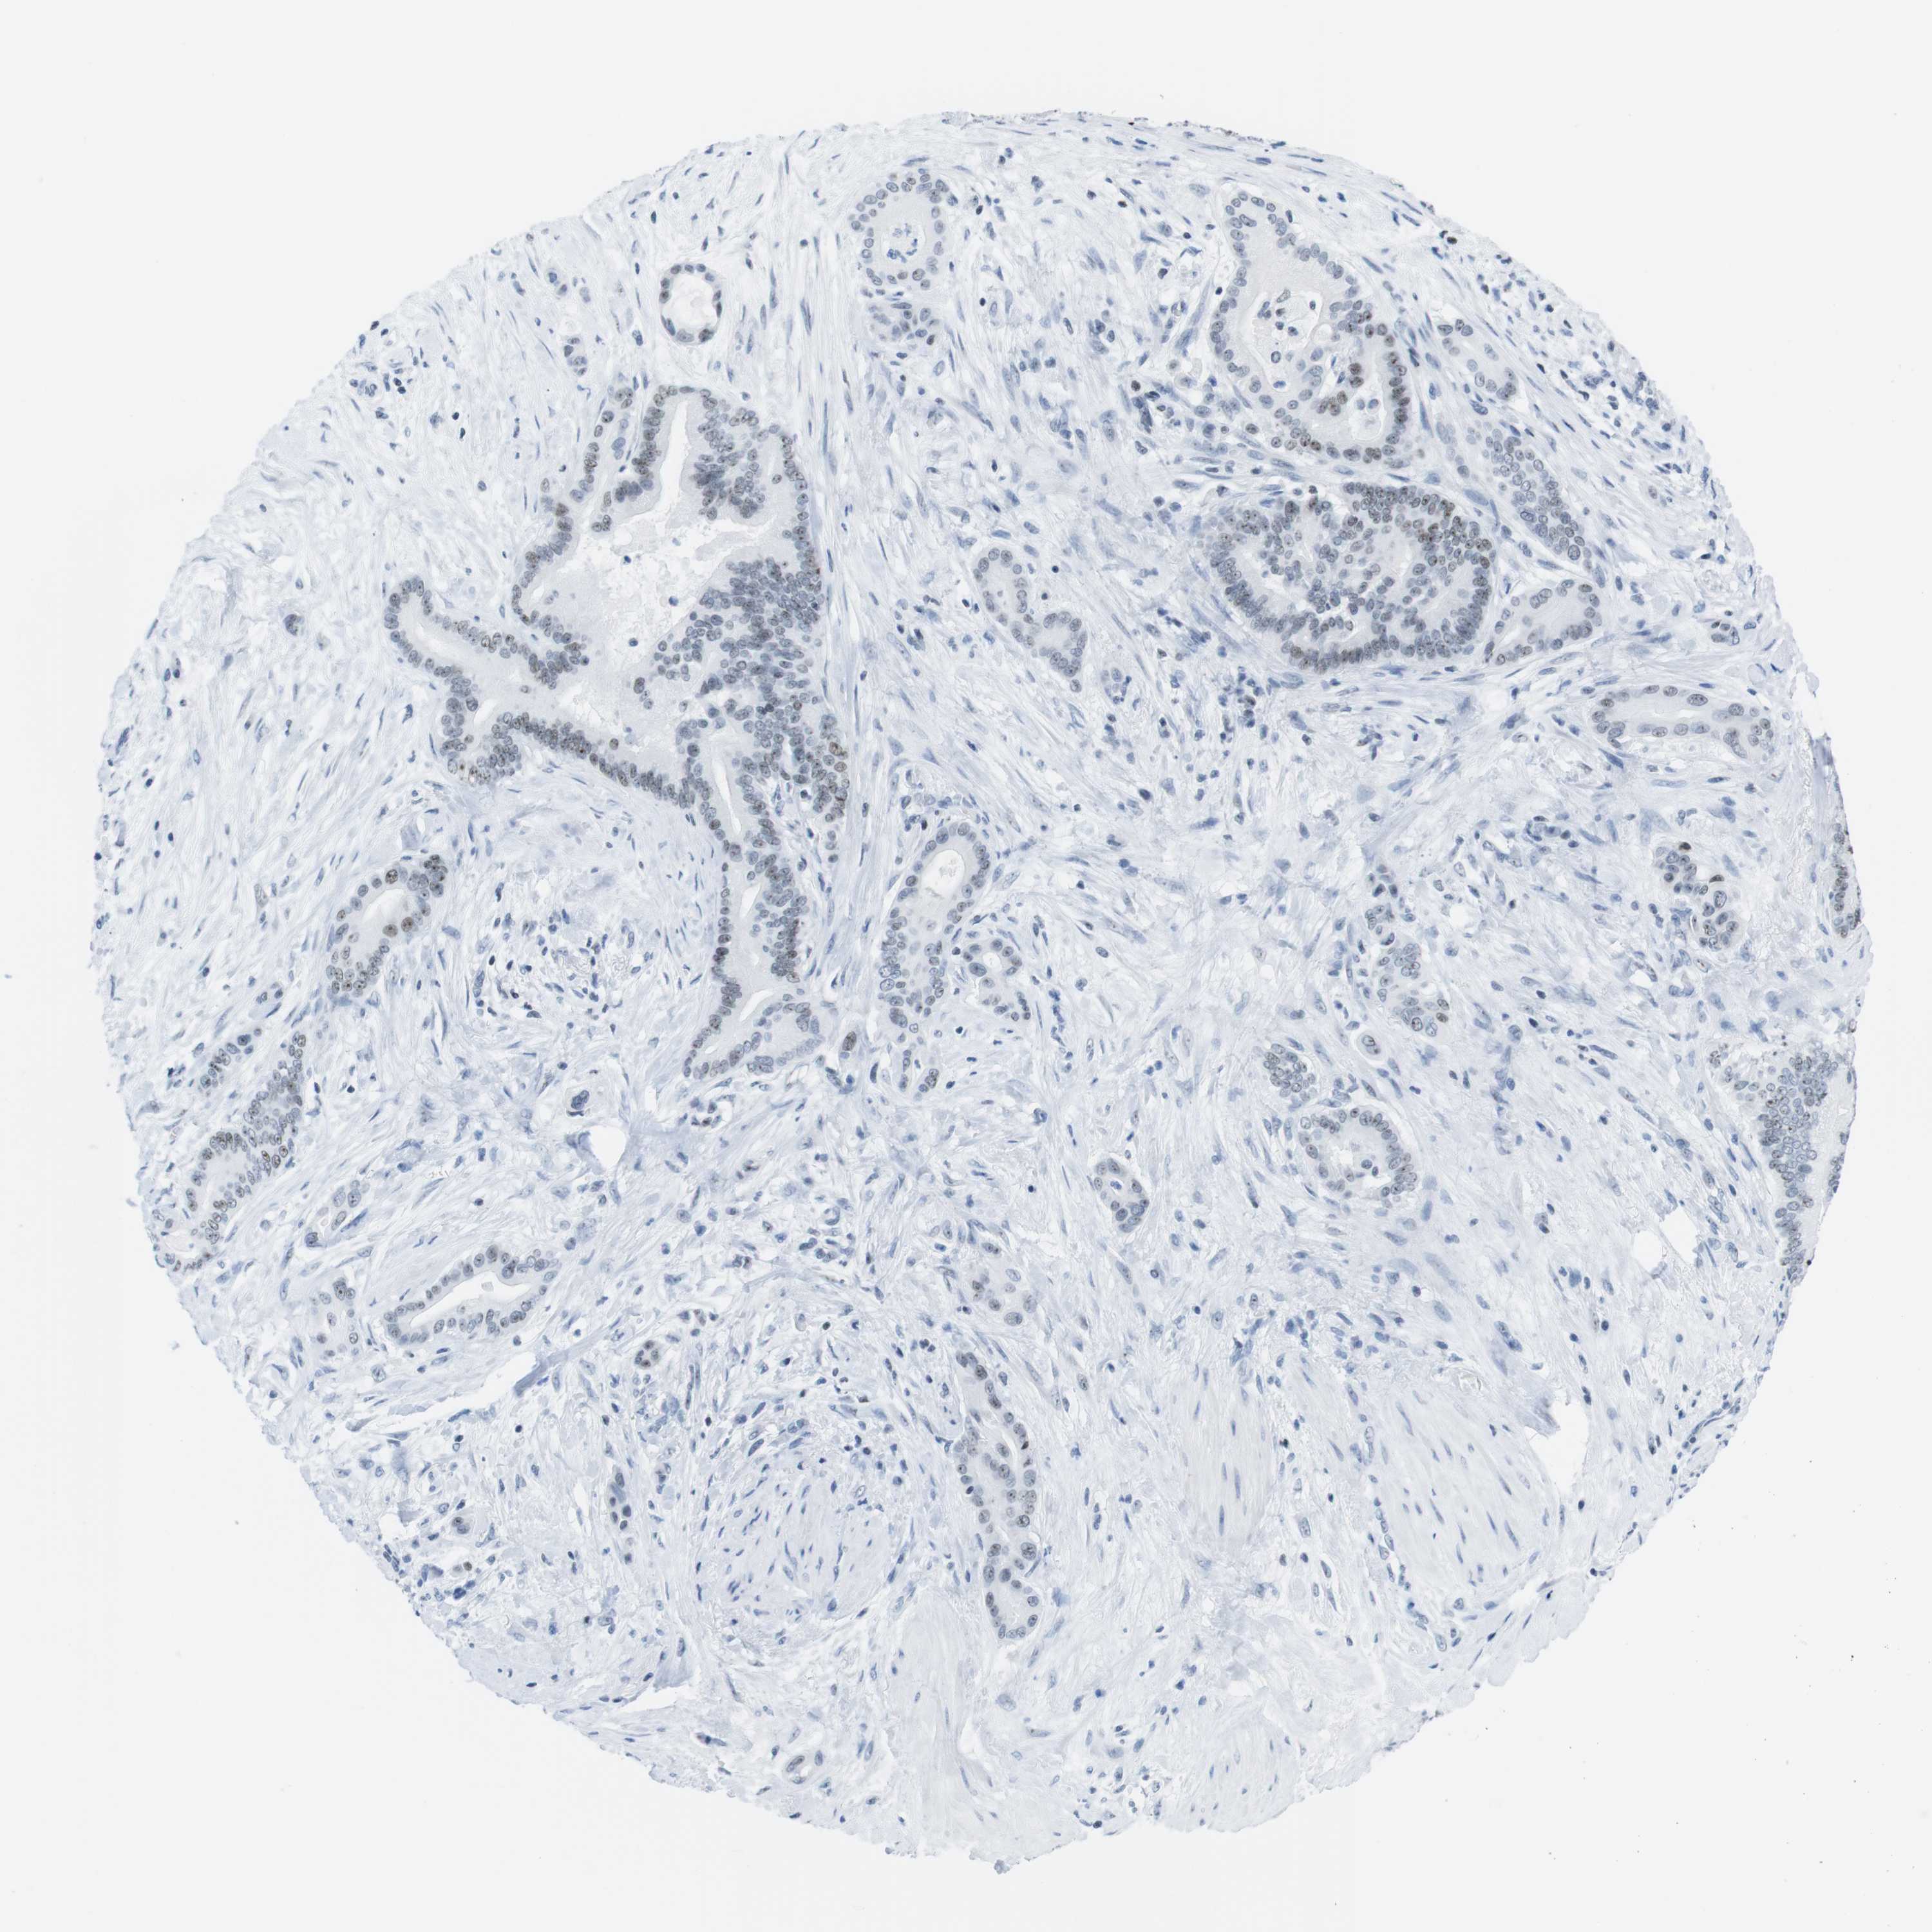

PANCREATIC CANCER - Protein expressioni

A mouse-over function shows sample information and annotation data. Click on an image to view it in a full screen mode. Samples can be filtered based on level of antibody staining by selecting one or several of the following categories: high, medium, low and not detected. The assay and annotation is described here.

Note that samples used for immunohistochemistry by the Human Protein Atlas do not correspond to samples in the TCGA dataset.

Antibody stainingi

Antibody staining in the annotated cell types in the current human tissue is reported as not detected, low, medium, or high, based on conventional immunohistochemistry profiling in selected tissues. This score is based on the combination of the staining intensity and fraction of stained cells.

Each image is clickable and will lead to virtual microscopy that enables deeper exploration of all samples and also displays staining intensity scores, fraction scores and subcellular localization as well as patient and tissue information for each sample.

HPA035735

HPA035736

CAB015382

CAB075728

CAB075729

Staining

High

Medium

Low

Not detected

Intensity

Strong

Moderate

Weak

Negative

Quantity

>75%

75%-25%

<25%

None

Location

Nuclear

Cytoplasmic/membranous

Cytoplasmic/membranous,nuclear

Adenocarcinoma, NOS